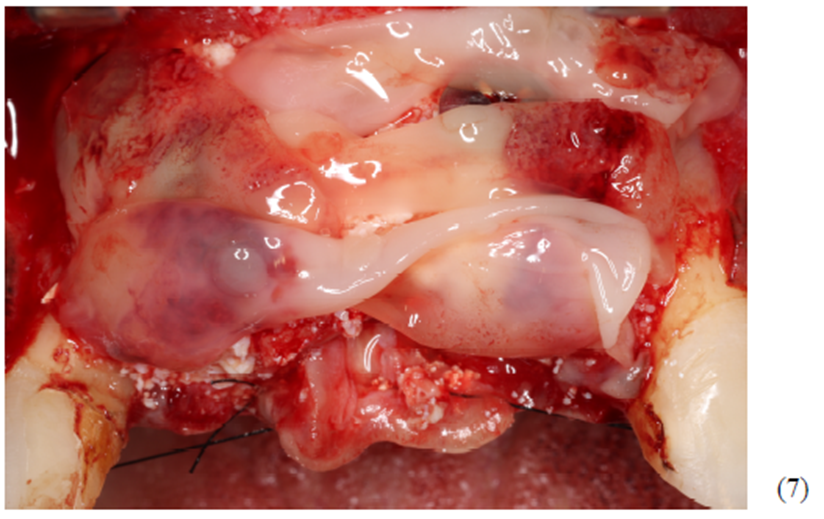

Foram colocados dois gramas de biomaterial de lenta reabsorção preenchendo toda cavidade até a delimitação da cabeça dos parafusos (Figuras 5 e 6). Antes do fechamento completo da ferida cirúrgica, colocamos membranas de PRF para auxílio na reparação tecidual e proteção do material de enxerto (Figura 7). Para fechamento da ferida cirúrgica, usamos fio do tipo Cytoplast, fornecido pela Implacil De Bortoli. É de extrema importância sua utilização, pois o fio apresenta excelente elasticidade, acompanhando edema cirúrgico pós-operatório, o que diminui o risco de deiscência no pós-operatório.